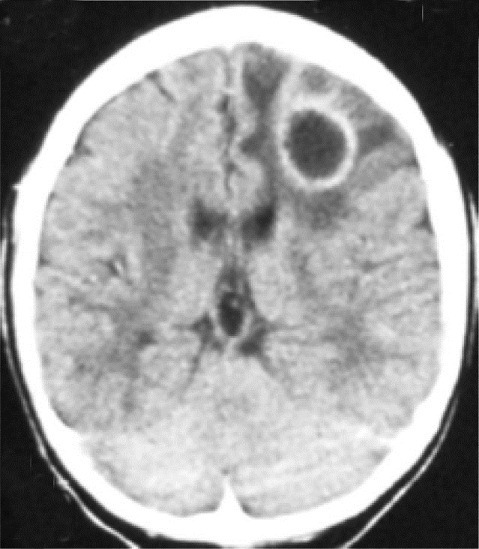

Ring enhancing lesions on CT from lymphoma

| current | 11:25, 30 July 2016 | ![]() | 479 × 549 (256 KB) | Neil.m.young (Talk | contribs) | Ring enhancing lesions on CT from lymphoma |